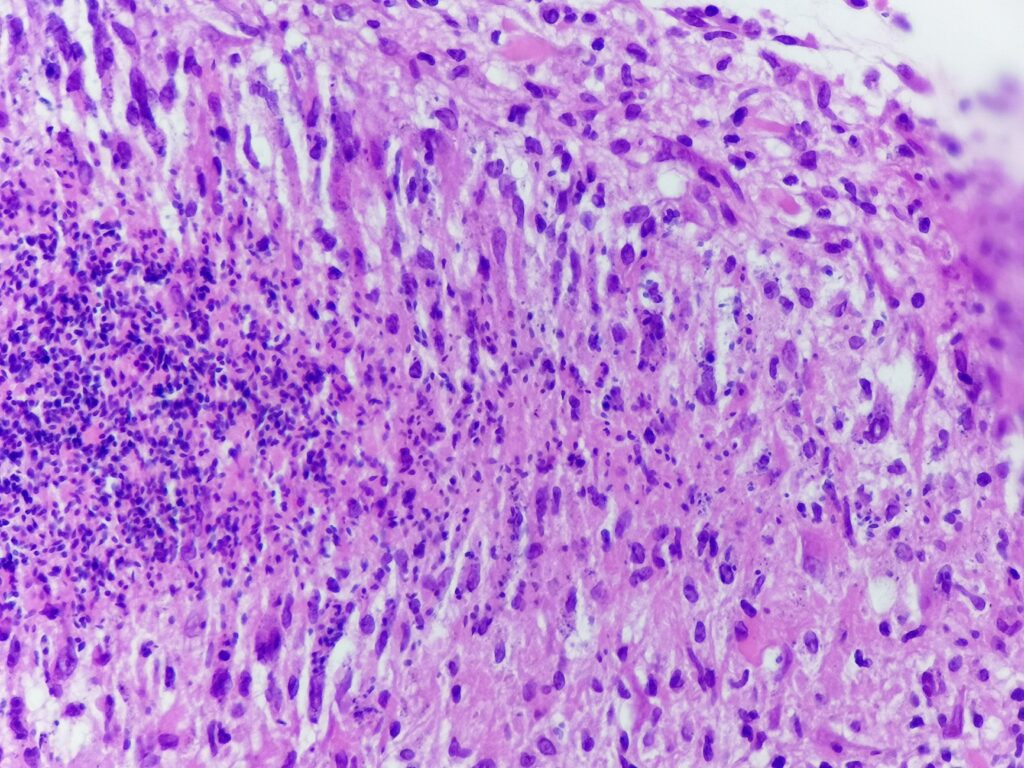

Obrazy mikroskopowe:

Cechy charakterystyczne:

- cienkościenna torbielowata struktura składająca się z tkanki łącznej (krzyżyk) wysłana jednowarstwowym nabłonkiem (czerwona strzałka) od kostkowego po walcowaty, z pojedynczymi komórkami rzęskowymi – torbiel nasienna patrz przypadek nr 105. SMP

- poza światłem zmiany obecne są plemniki (gwiazdka) z otaczającym odczynem z histiocytów (komórki o owalnym lub okrągłym jądrem komórkowym stosunkowo obfitej lekko kwasochłonnej cytoplazmie, niebieska strzałka), nieliczne limfocyty i komórki wielojądrowe (zielona strzałka) – ziarniniak

- brak komórek atypowych, martwicy centralnej, grzybów bądź innych mikroorganizmów

Ziarniniak nasienny (sperm granuloma)